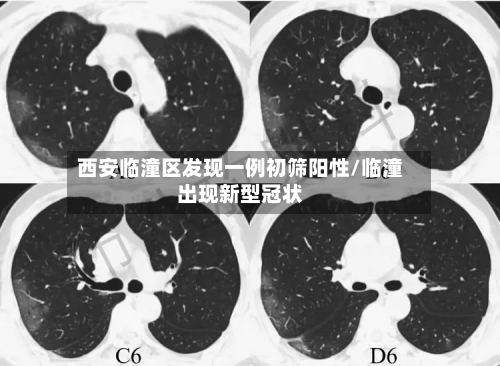

西安临潼区发现一例核酸初筛阳性人员,近来接触人员情况如何?

近来接触人员都已经按照规定报备 ,并且配合疫情防控的要求,接受隔离了。西安临潼区区发现一例核酸初筛阳性人员,近来已这名阳性人员有过间接性接触的人员基本上都已经按照当地的防疫规定向有关部门报备,并且配合相应的防疫措施 ,接受了隔离管控 。

月18日,西安市临潼区在集中隔离人员中发现一例无症状感染者。该病例曾于4月16日12:43至13:37在马额街道有活动轨迹,先后到马额街道旺盛达门业 、鸿运建材商店购买建材等。

临潼区紧急寻人 4月18日 ,西安市临潼区在集中隔离人员中发现一例无症状感染者。该病例曾于4月16日12:43至13:37在马额街道有活动轨迹,先后到马额街道旺盛达门业 、鸿运建材商店购买建材等 。

〖壹〗 、临潼区紧急寻人 4月18日,西安市临潼区在集中隔离人员中发现一例无症状感染者 。该病例曾于4月16日12:43至13:37在马额街道有活动轨迹 ,先后到马额街道旺盛达门业、鸿运建材商店购买建材等。请4月16日以来去过马额街道的人员,立即就近向所在村委会(社区)或疫情防控部门进行报备,并落实从4月16日到21日5天3次核酸检测要求。